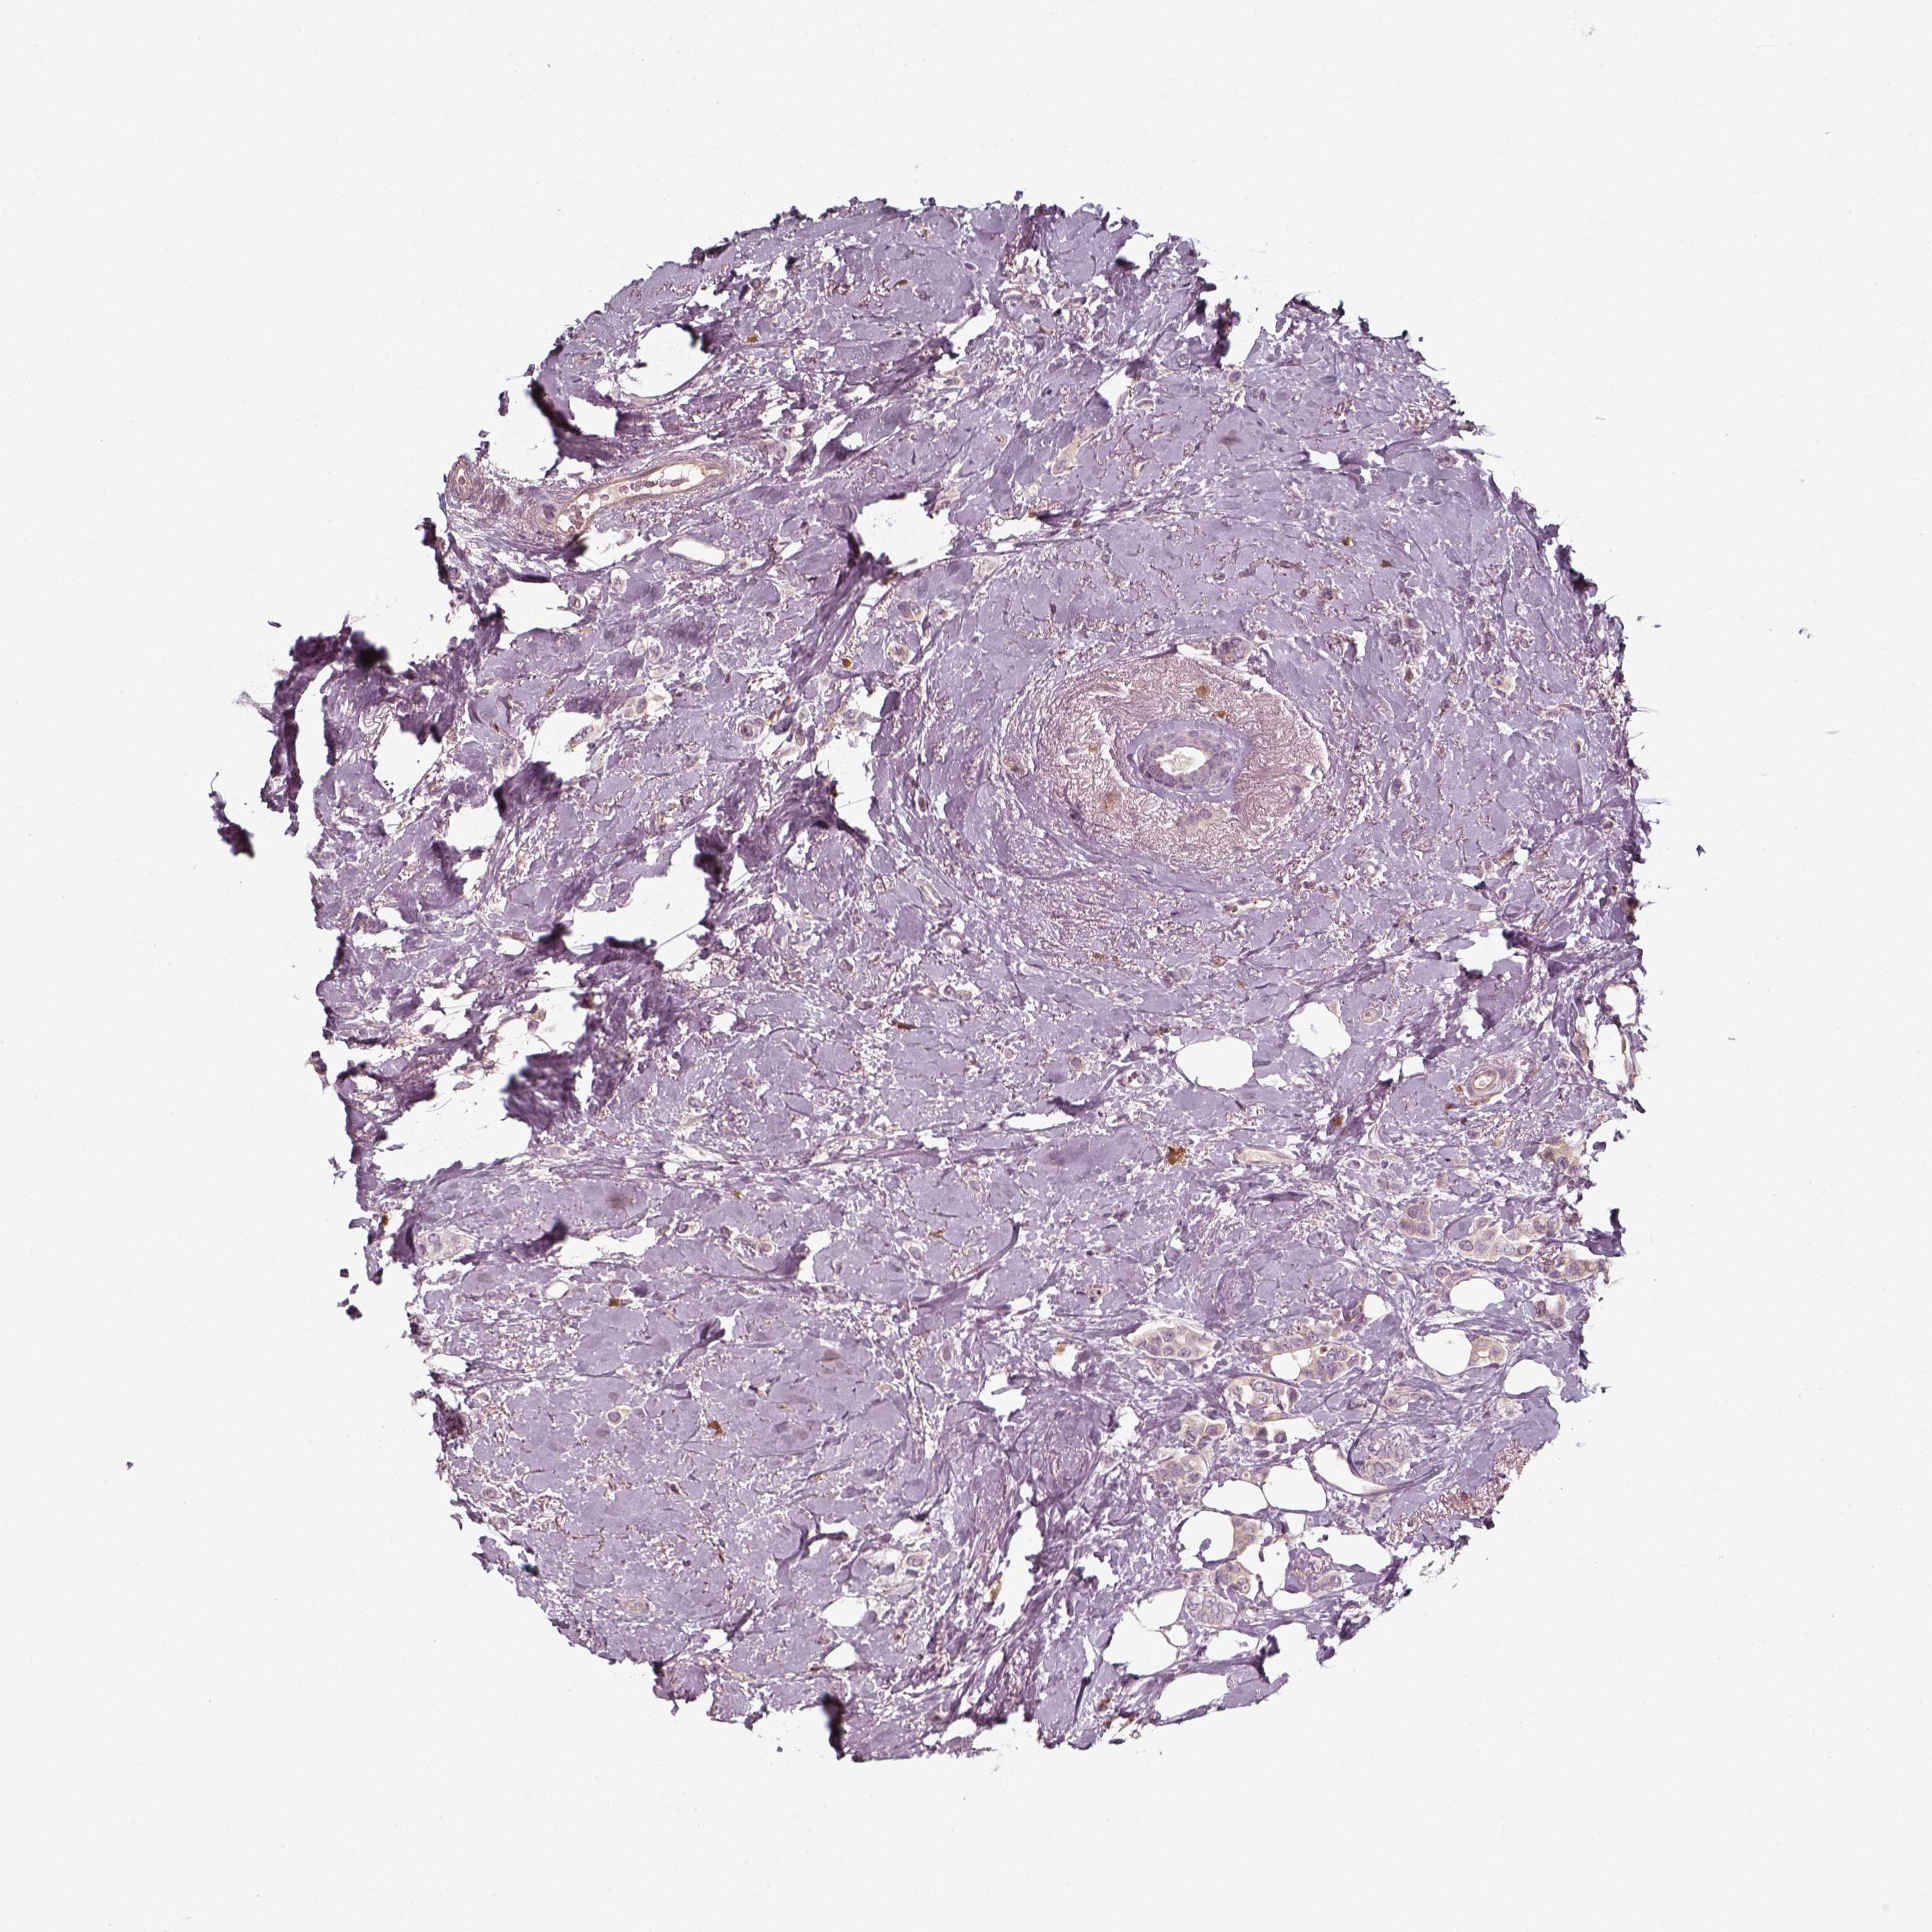

CANCER BREAST CANCER Show tissue menu

BRCA TCGA BRCA VALIDATION PROTEIN EXPRESSION